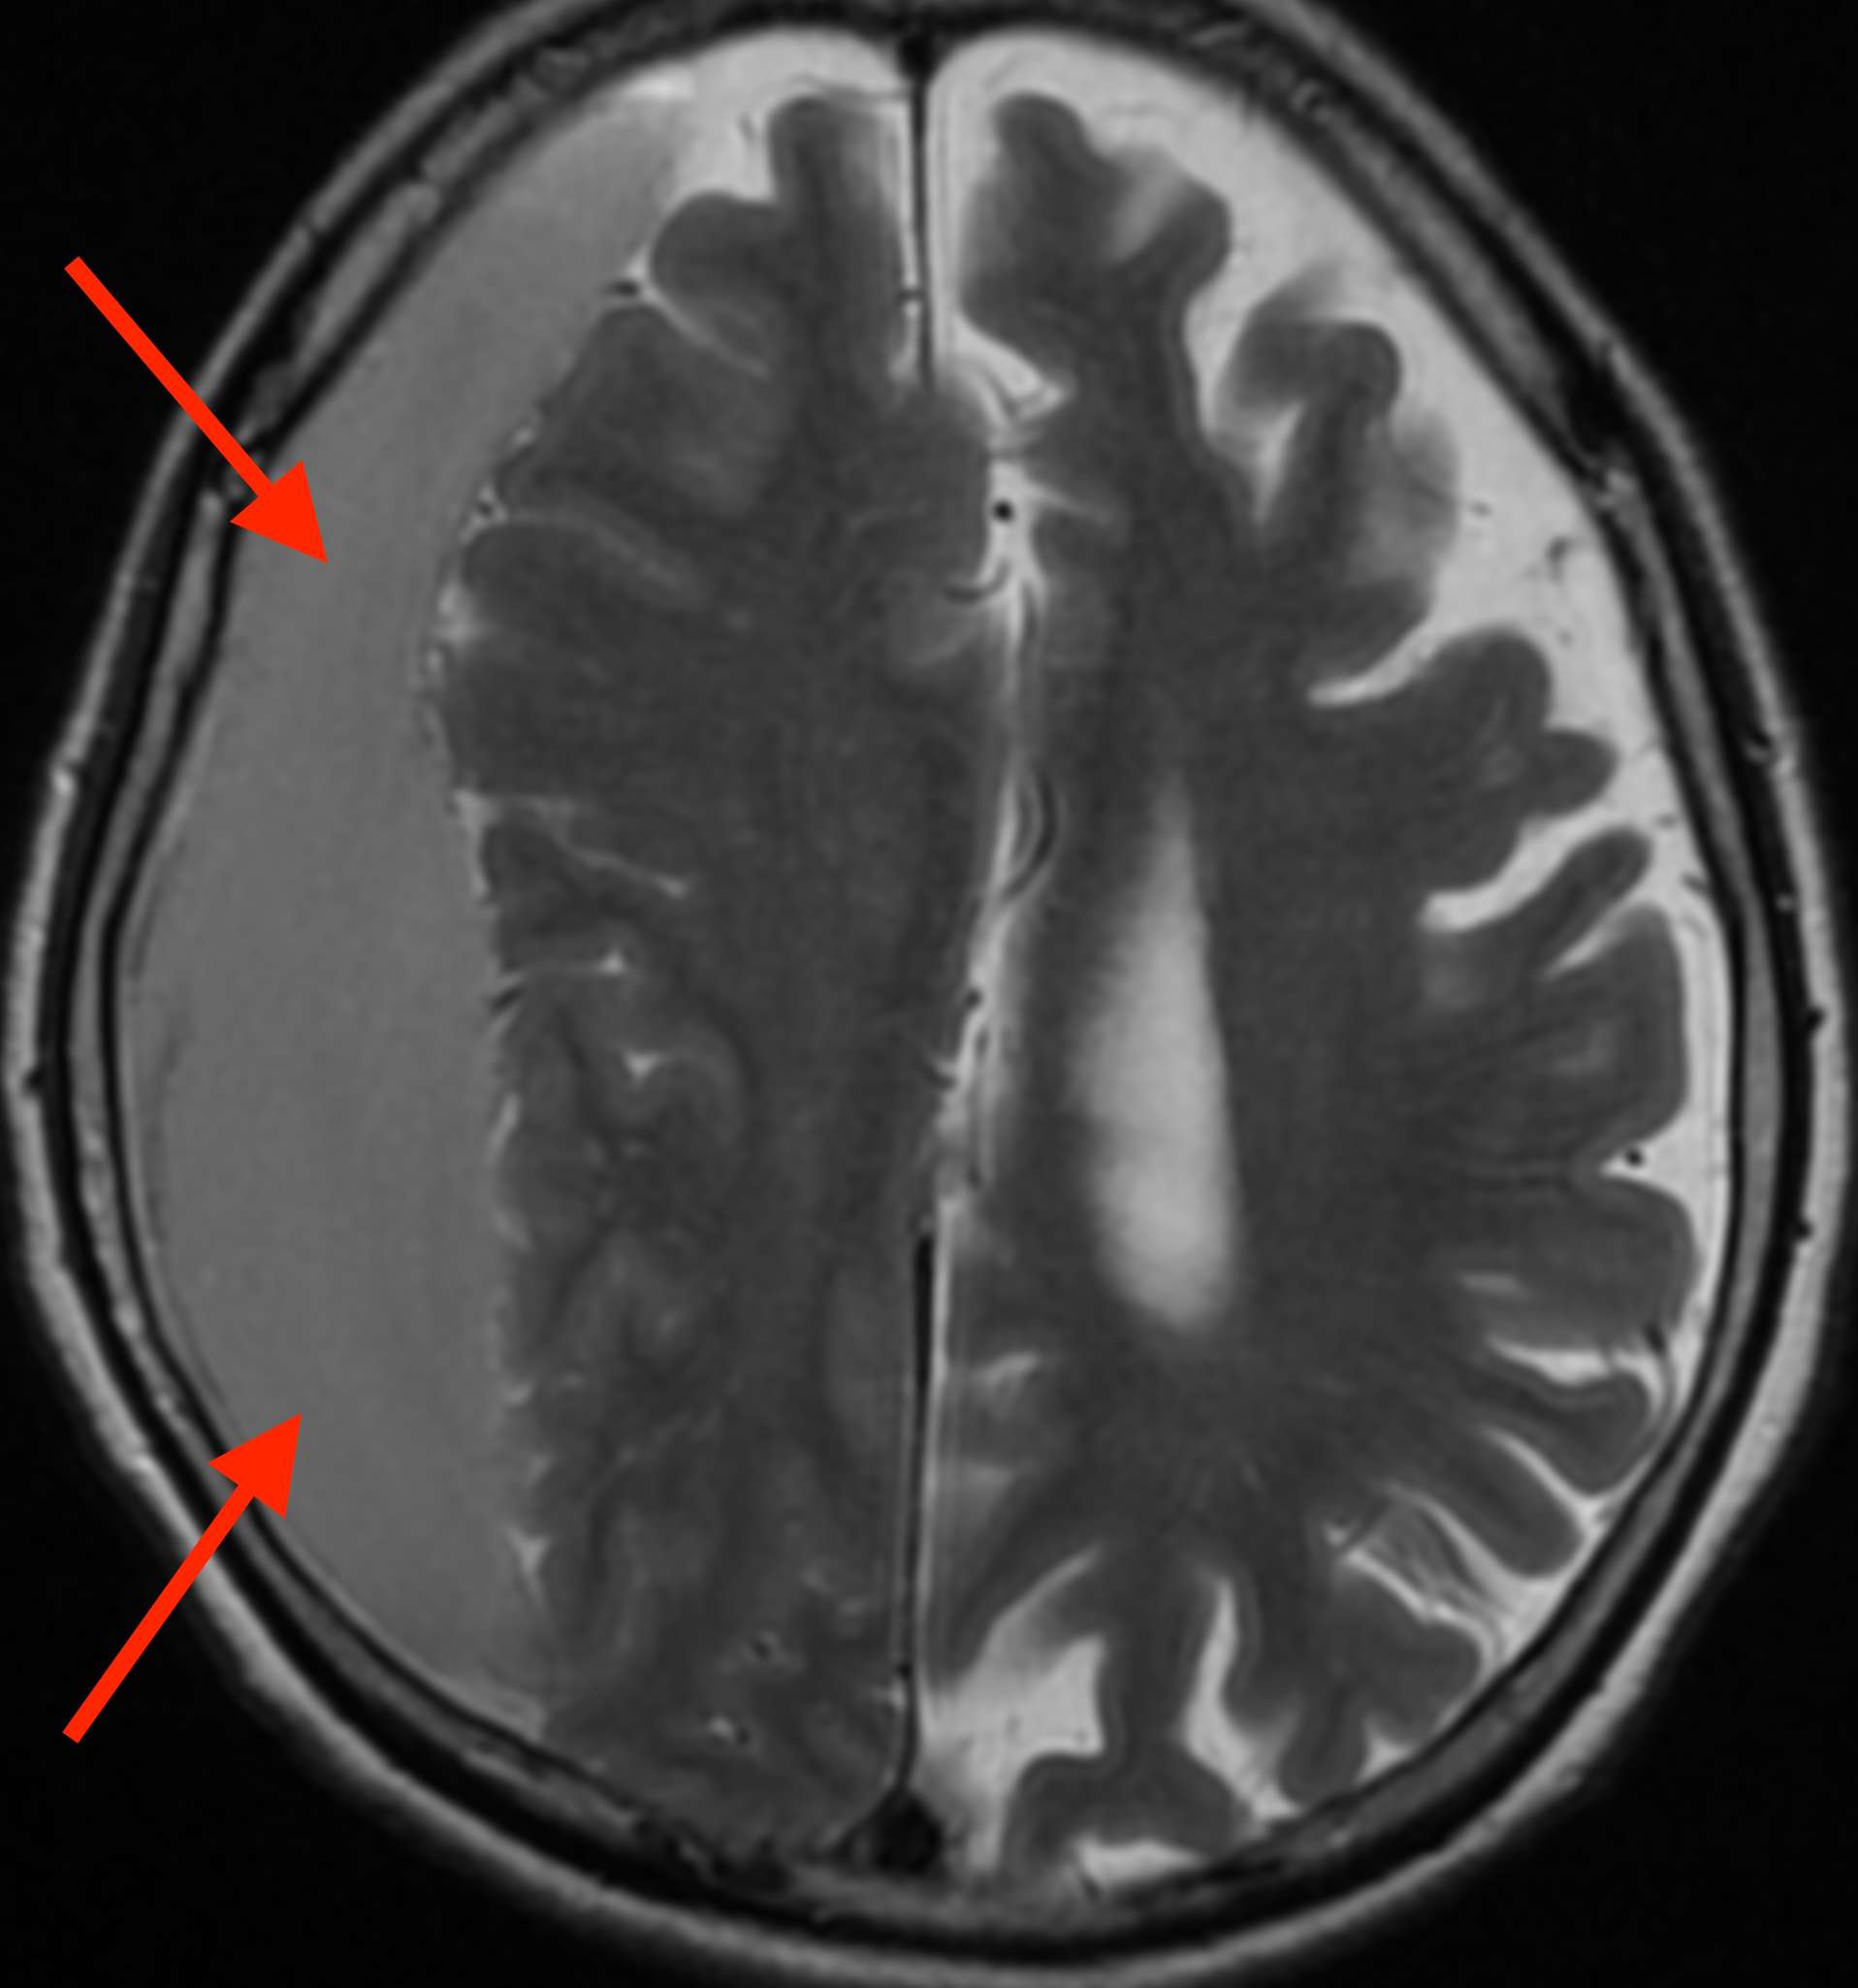

MRI検査をしたところ、

脳の右側に血液が貯まっていて脳を圧迫しており、慢性硬膜下血腫2) という状態です。

慢性硬膜下血腫は、頭蓋骨の内側にある硬膜の静脈が破れて出血した状態です。

強く頭をぶつけた後に生じる事が多いですが、原因がはっきりしない場合もあります。しかし、頭をぶつけた後1ヶ月以上たってから生じる事もあります。

特に高齢者の場合には、転んだり頭をぶつけた事自体を覚えていなかったり、痛みの感受性が鈍くなっていたりするため、「頭痛」という症状が隠れてしまう事があります。